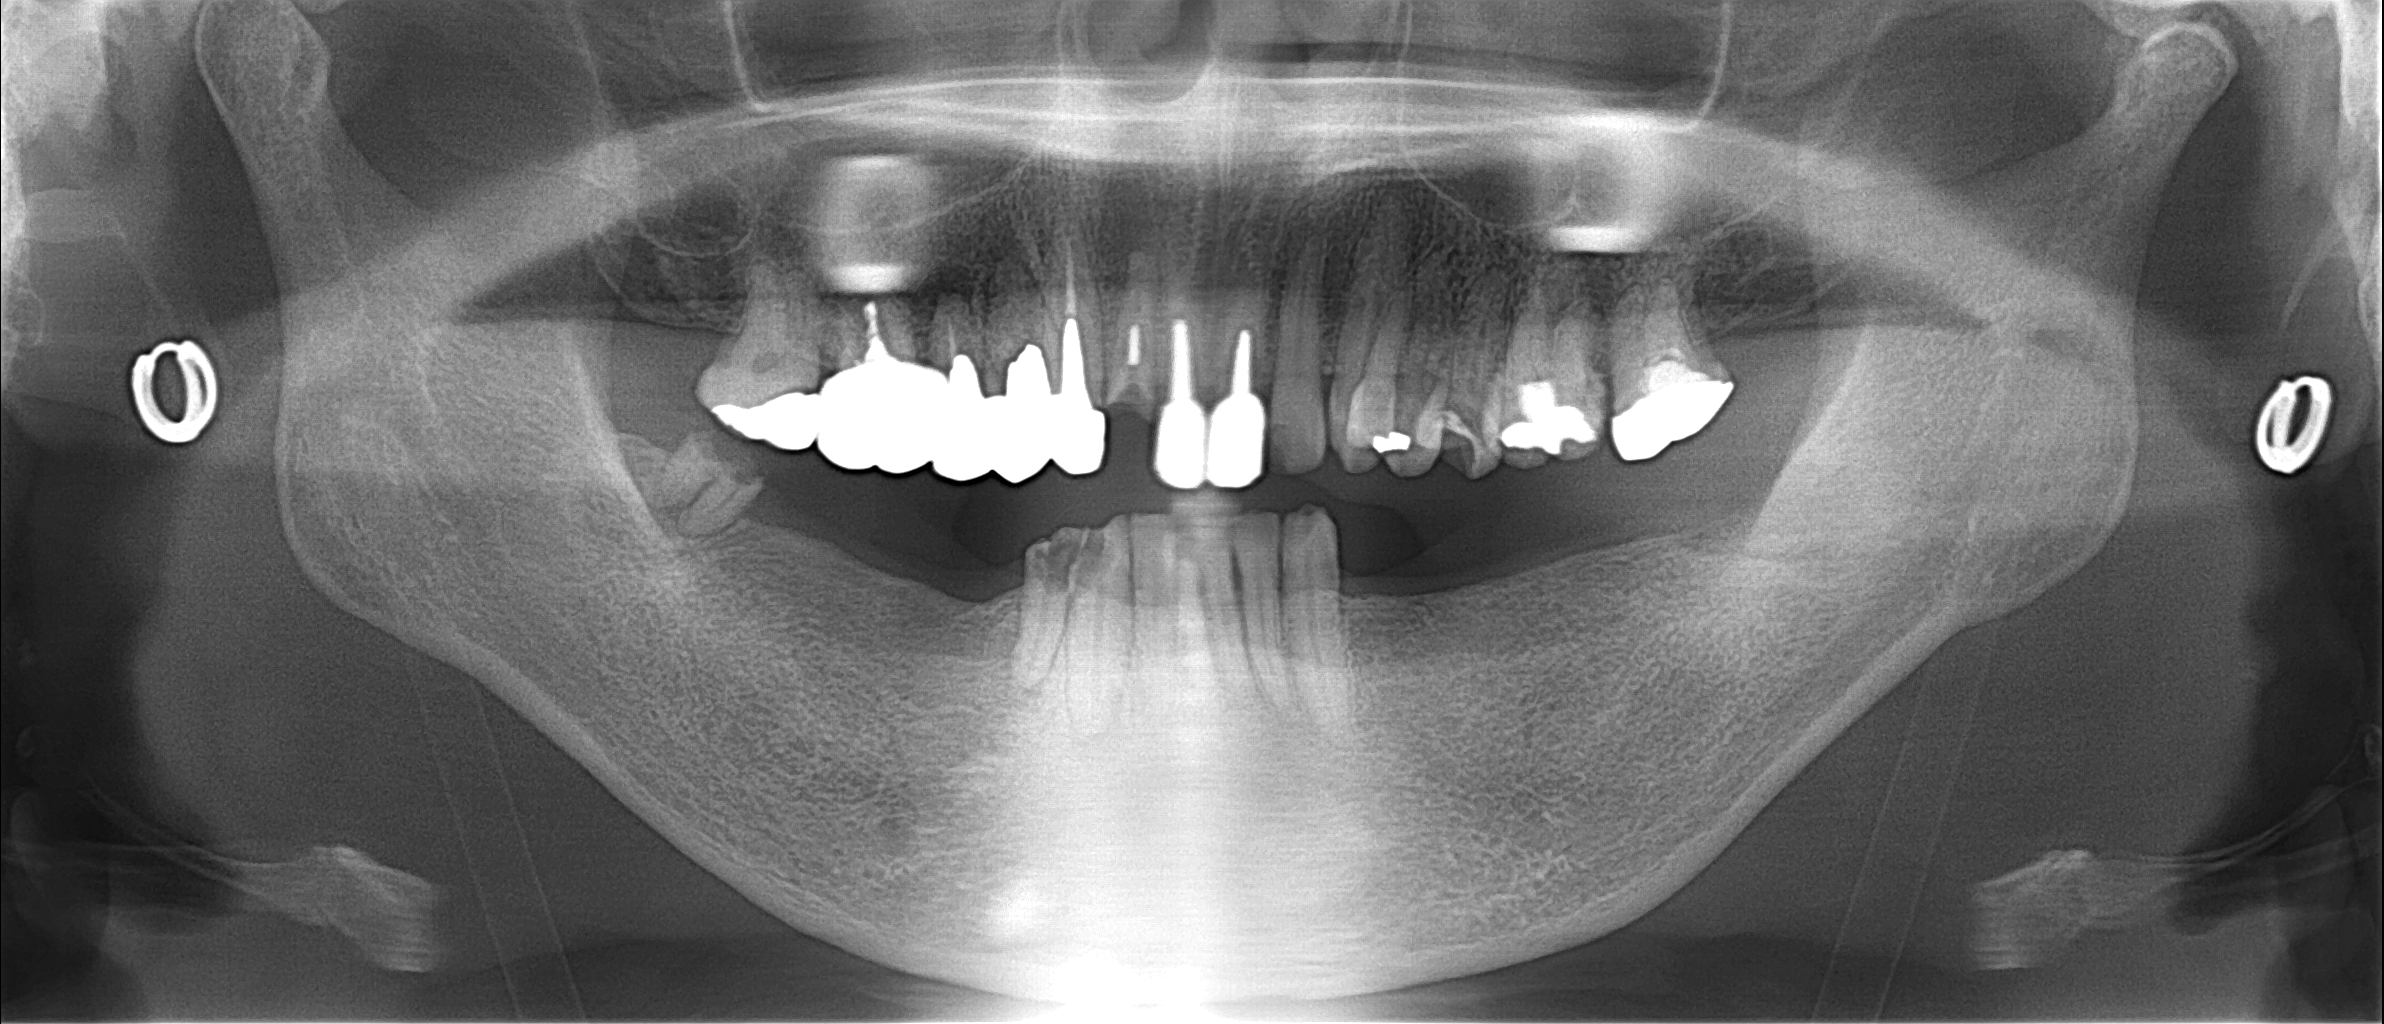

初診時レントゲン

↑のように下の奥歯がない状態の場合は

前歯でご飯を食べるので

上の前歯に強い突き上げる力が作用します。

まずは右下の赤い丸の部分に埋入させてもらいました。

上の奥歯と下の歯ぐきが引っ付きそうになっている

長期間、奥歯がない状態だったようで

レントゲンからは分りにくいかもしれませんが

咬んだ時に上の奥歯と下の歯ぐきが

引っ付きそうになっています。